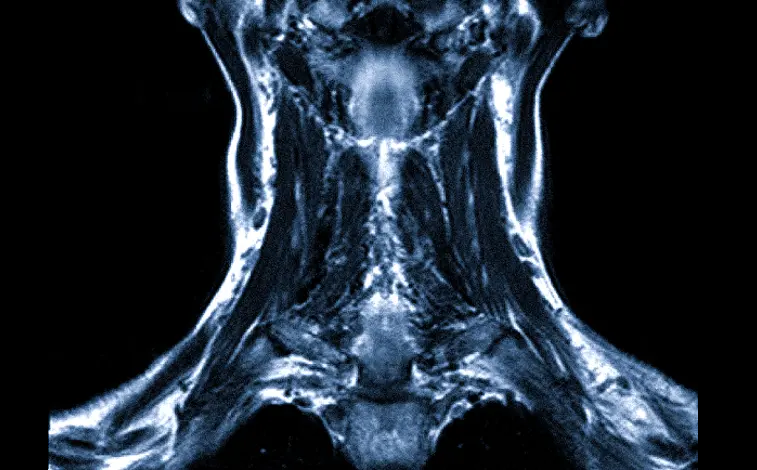

Сканы томографа представляют собой цифровые изображения в черно-белом формате. Съемку производят послойно под разными углами с небольшим отступом срезов друг от друга. Каждый снимок – это отдельный срез конкретного участка шеи. Благодаря высокому разрешению и детализации, на снимках видны даже микроскопические элементы следующих органов и тканей:

В особом режиме сканирования кости становятся менее заметными («прозрачными»), поэтому не перекрывают мелкие очаги воспаления или повреждения в соседних мягкотканных структурах.